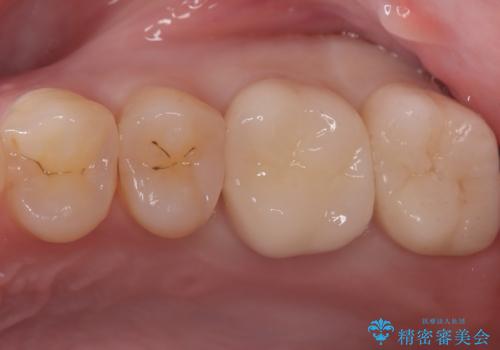

奥歯の銀歯を美しく一新!歯の破折を防ぐセラミッククラウン

担当医 河口智英